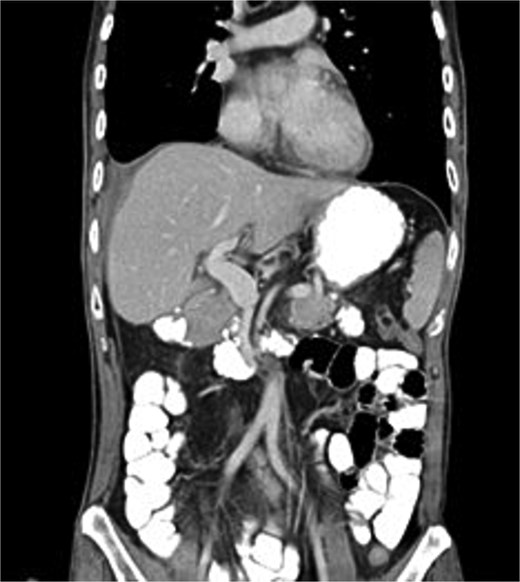

This combined approach achieved effective biliary diversion and clinical improvement. Total biliary drainage, including duodenostomy and ENBD output, stabilized at ~500 ml/day. During this period, oral intake was gradually resumed, supplemented by jejunostomy feeding. Once biliary output plateaued and clinical stability was achieved, the ENBD catheter was removed 2 months later. All external drainage tubes, including the duodenostomy, were subsequently removed. The patient advanced to full oral intake, jejunostomy feeding was discontinued, and the tube was removed without complication. Recovery was uneventful, with restoration of bowel function. Postoperative CT (Fig. 5) confirmed an intact gastrointestinal tract without obstruction.

Post-intra-abdominal/intestinal with non-obstructive adhesion, no detectable apparent oral contrast leak, and no pancreatobiliary ductal dilatation.